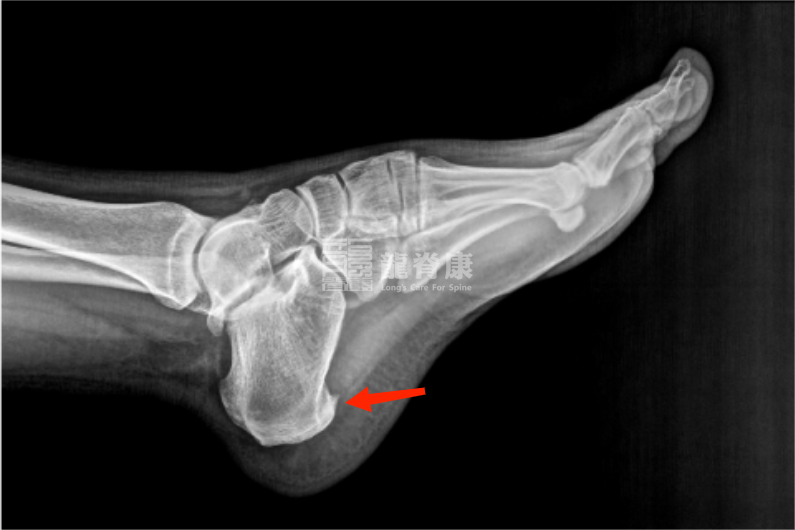

4、足跟骨刺

足跟骨刺是跟骨下缘的异常骨质增生,本身可能不直接引起疼痛,但刺激周围软组织时会引发疼痛和炎症。

主要表现为足跟痛和行走困难,可能伴足底广泛压痛。行走或站立时加重,休息后缓解。主因长期过度负重和不适当锻炼,年龄增长导致的跟骨退行性改变也是常见原因。

医生通常会通过体格检查和影像学检查(如X光、超声或MRI)来明确诊断。